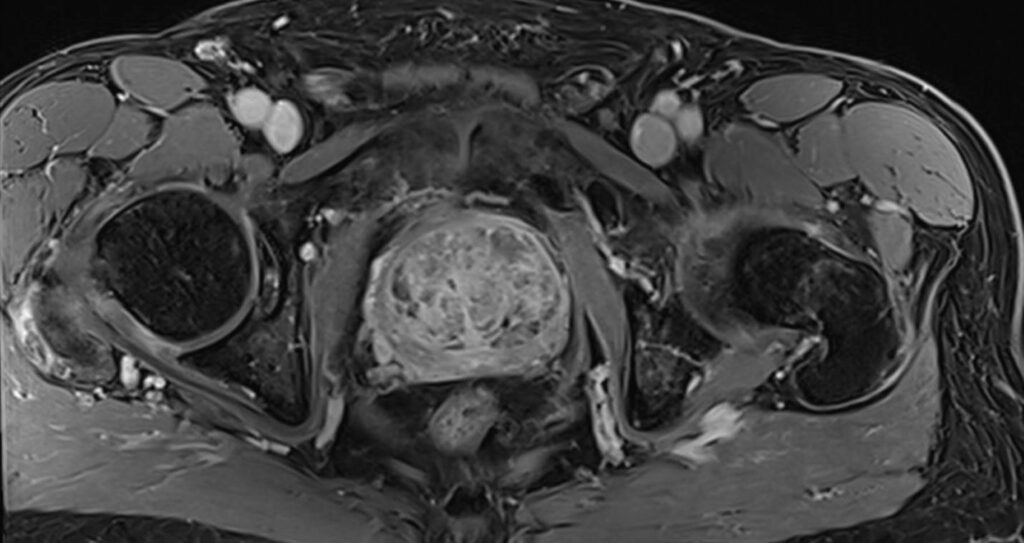

Die Magnetresonanztomographie der Prostata, kurz MRT Prostata, ist eine nicht-invasive und völlig schmerzfreie Untersuchung des Organs. Aufgrund der Komplexität der Prostatadrüse und der Vielfalt möglicher Veränderungen ermöglicht die MRT eine detaillierte Darstellung des Prostatagewebes. Die MRT Prostata spielt eine entscheidende Rolle bei der frühzeitigen Erkennung von Veränderungen und ermöglicht eine präzise Diagnose.

Die Magnetresonanztomographie, kurz MRT, ist eine nicht-invasive und völlig schmerzfreie Untersuchung der Prostata.

Über Magnetfelder wird ohne Strahlenbelastung das Körperinnere mit einem exzellenten Weichteilkontrast in hoher Auflösung dargestellt und ermöglicht eine präzise Beurteilung der Gewebeveränderungen.

Die MRT der Prostata erfolgt „multiparametrisch“ mit standardisierten Protokollen.

Mittels eines Bewertungssystems (PI-RADS-Score) werden die MRT-Bilder der Prostata ausgewertet und klassifiziert, als eine standardisierte Interpretation zur detaillierten Einschätzung des Prostatakrebsrisikos.

Die Prostata wird mit hochaufgelösten MRT-Bildern in allen Ebenen und mehreren Ansichten dargestellt sowie mittels verschiedener Funktionsmessungen analysiert.

Zunächst liegt der Fokus darin, in der Struktur und Signalgebung verändertes Drüsengewebe von gesundem Gewebe abzugrenzen. Als nächstes gilt es, verändertes Gewebe mit Funktionsmessungen (wie z.B. Zelldichte und Durchblutung) zu charakterisieren. Die diffusionsgewichtete MRT-Sequenz macht sichtbar, ob in verändertem Gewebe eine erhöhte Zelldichte – wie bei einem Prostatakarzinom – vorliegt. Die dynamische kontrastmittelangehobene MRT-Sequenz lässt Prostatakrebsareale mit einer erhöhten Durchblutung abgrenzen.